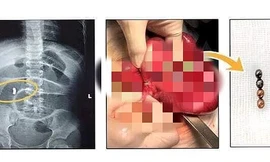

TPO - Ngày 19/9, BS Nguyễn Hiền, khoa Ngoại Tổng hợp, Bệnh viện Nhi Đồng 2 TPHCM cho biết, tại đây vừa tiếp nhận và can thiệp cho trường hợp trẻ bị thủng ruột, nguy hiểm tính mạng vì nuốt nam châm đồ chơi.

TPO - Ngày 9/7, thông tin từ Bệnh viện Nhi Đồng 2 TPHCM cho biết, tại đây vừa tiếp nhận, can thiệp cho một bệnh nhi bị thủng ruột do nuốt đồ chơi làm bằng nam châm.

TPO - Nhập viện trong tình trạng đau bụng, nôn ói, bí đại tiện, bệnh nhi được bác sĩ kiểm tra hình ảnh thì phát hiện trong đường tiêu hóa có nhiều dị vật cản quang. Các bác sĩ đã tiến hành phẫu thuật lấy ra 20 viên nam châm và cắt bỏ đoạn ruột bị hoại tử.

TPO - Nhập viện trong tình trạng đau bụng quằn quại, bệnh nhi được bác sĩ kiểm tra phát hiện trong đường tiêu hóa có nhiều dị vật xếp thành hình vòng tròn. Trong quá trình phẫu thuật lấy dị vật, bác sĩ phát hiện 14 viên nam châm hít vào nhau đã khiến bệnh nhi bị thủng ruột.

TPO - Được bạn cùng lớp cho 5 viên bi nam châm nhưng sợ bị cô phát hiện, tịch thu, bé gái 6 tuổi ngậm vào miệng để giấu. Tuy nhiên, trong lúc sơ ý, cháu đã nuốt cả 5 viên bi vào dạ dày và phải nhập viện cấp cứu.

TPO - Trẻ ngậm trong miệng rồi nuốt lúc nào không biết, đến khi đau đớn quằn quại phải nhập viện thì đã bị thủng ruột bởi 2 viên bi nam châm gây ra. Bác sĩ cảnh báo, nuốt dị vật là tai nạn rất nguy hiểm có thể cướp đi sinh mạng của bệnh nhi.

TPO - Nhân dịp sinh nhật, bé gái được mẹ mua cho một bộ đồ chơi có nhiều viên bi nam châm. Trong lúc chơi đùa, bé đã vô tình nuốt phải 4 viên bi khiến ruột bị tắc, nguy kịch đến tính mạng.